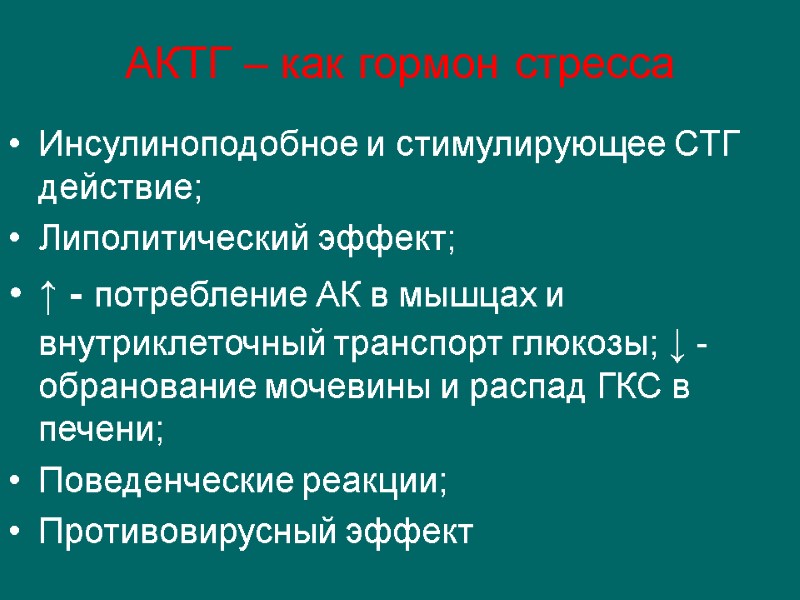

АКТГ – как гормон стресса Инсулиноподобное и стимулирующее СТГ действие; Липолитический эффект; ↑ - потребление АК в мышцах и внутриклеточный транспорт глюкозы; ↓ - обранование мочевины и распад ГКС в печени; Поведенческие реакции; Противовирусный эффект